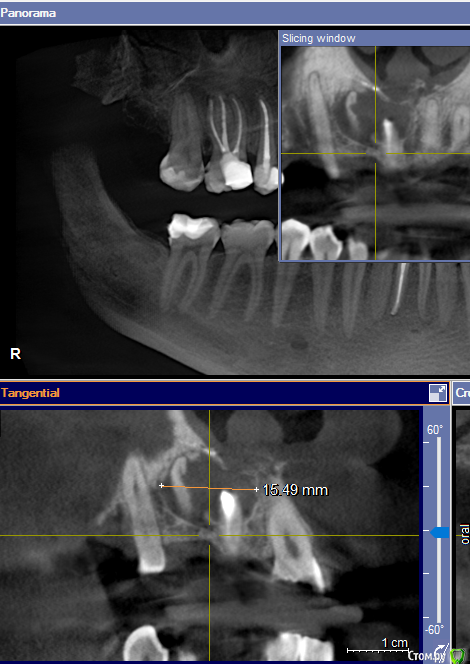

Wintermute Опубликовано 18 мая, 2016 Поделиться Опубликовано 18 мая, 2016 Обнаружили кисту и хирург говорит что нужно удалять два передних зуба, один пролеченный возможно еще в СССР (и видимо является причиной проблемы), второй здоровый, но киста видимо как-то "отъела" часть корня. У меня возникли некоторые сомнения что удаление необходимо, интернет пишет что киста лечится сейчас резекцией корня зуба, а сами зубы стараются сохранить. Может ли кто-нибудь сказать возможен ли вариант с сохранением зубов (или одного) в моем случае? Ссылка на комментарий

red_butler Опубликовано 19 мая, 2016 Поделиться Опубликовано 19 мая, 2016 Проверить 1.2 на витальность, скорее всего эндо лечение. Я бы все таки сделал цистэктокию с РВК 1.1 и ретроградным пломбированием. 1 Ссылка на комментарий

red_butler Опубликовано 19 мая, 2016 Поделиться Опубликовано 19 мая, 2016 Спасибо за ответы. Т.е. если я правильно понял ситуация еще может позволить терапевтическое лечение (когда распломбируют канал и удаляют пытаются избавиться от инфекции)? Имеет смысл тогда помучить вопросами терапевта. Подождем что скажут терапевты, по мне канал 1.1 и так пере расширен. Ссылка на комментарий

St. Опубликовано 19 мая, 2016 Поделиться Опубликовано 19 мая, 2016 Еще одно перелечивание 1.1 не переживет, там от стенок и так мало осталось и по ширине и по длине. Я бы за него не боролась.У 1.2 шансов больше, но смущает его резорбция, за него если есть желание ещё можно побороться.Если готовы попробовать и найдете доктора можно попытаться. Само собой лечение будет негарантийным и достаточно дорогим, хотя есть шанс на успех.Если хотите гарантий - то терапевт вам не помощник. 2 Ссылка на комментарий